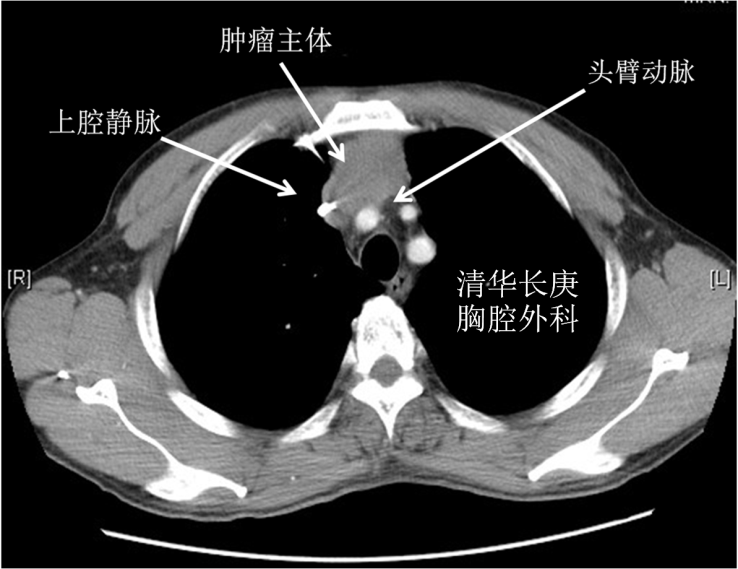

右肺上叶癌侵及心脏大血管分期为T4,常被认为无法切除,患者失去手术机会。既往不断有尝试切除并获得较好预后的报道,但手术难度大、围术期死亡率高仍是主要问题。此患者就诊前曾于外院行气管镜活检,病理提示肺腺癌。同时未见远处转移,具备手术指征。久经转诊的多家医院均认为无法手术。患者临床表现以上腔静脉阻塞综合征为主(头面部肿胀、静脉曲张、呼吸困难),成功切除肿瘤才能得到缓解。

手术采用胸骨正中切口,进胸后细致分离肿瘤与胸骨间粘连,充分探查后可见肿瘤侵及肺门、左右无名及上腔静脉、右心房、心包及纵隔胸膜。陈东红主任认为为达到R0切除,需进行右全肺、上腔静脉切除,人工血管重建。材料采用Gore-Tex带环人工血管,先以人工血管建立左无名静脉-右心耳血管桥,进一步心包内切除右全肺及受肿瘤侵犯的部分右心房,手工牢固缝合右心房,整块切除肿瘤后搭右无名静脉-右心耳血管桥。进一步彻底清扫纵隔淋巴结。完成手术后可见人工血管充盈,心脏搏动有力,血液动力学指标平稳。切除肿瘤标本直径约8cm,手术时间约7小时。